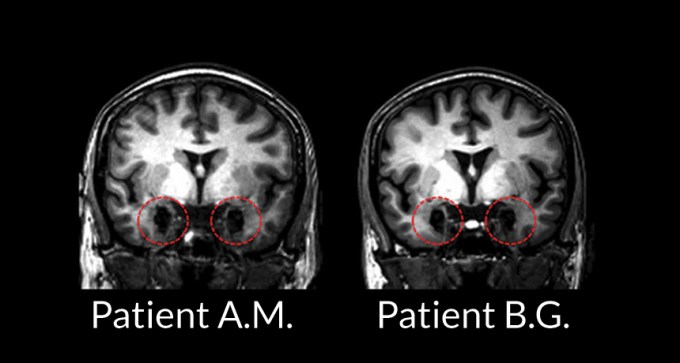

Brain holds more than one road to fear

A study on rare patients suggests that fear can take many paths through the brain.